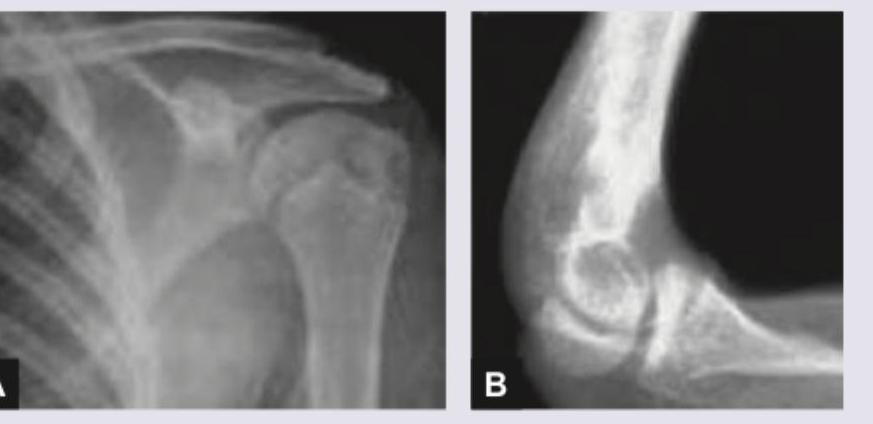

Question 7: Comment on age of the male patient:

- B. 12-14 years (Correct Answer)

Explanation: ***12-14 years*** - The radiographs show **open growth plates** (epiphyseal lines) in both the shoulder (A) and elbow (B), indicating the individual is still growing. - The presence of well-developed secondary ossification centers and significant but not fully fused physes is consistent with a male in the **mid-pubertal** range, typically observed between 12-14 years. *5-7 years* - At this age, many **secondary ossification centers** would just be appearing or still quite small, and the growth plates would be much wider and less defined than seen in the images. - The degree of skeletal maturation evident in the shoulder and elbow in the images surpasses that of a 5-7 year old. *17-19 years* - By this age, most **growth plates** in males, especially in key joints like the shoulder and elbow, would be largely **fused** or in the final stages of fusion. - The distinct open physes seen in both images rule out this age range, as significant growth is still occurring. *>25 years* - In an individual over 25 years, **all growth plates** would be completely **fused**, and there would be no visible epiphyseal lines. - The presence of clear, open growth plates in the images definitively excludes an adult age.